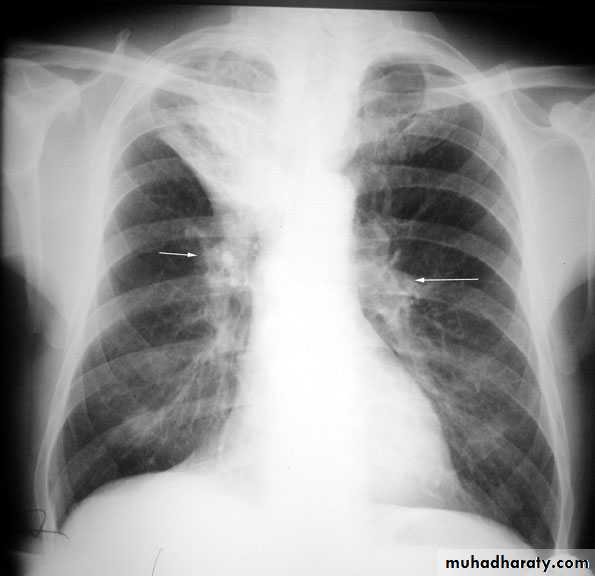

Pulmonary nodule /s1) Bronchogenic CA ( spiculated )

2)Metastasis ( multiple & different size & distribution )

3) Tuberculoma

4) hamartoma

Both are : solitary , peripheral & contain calcification )